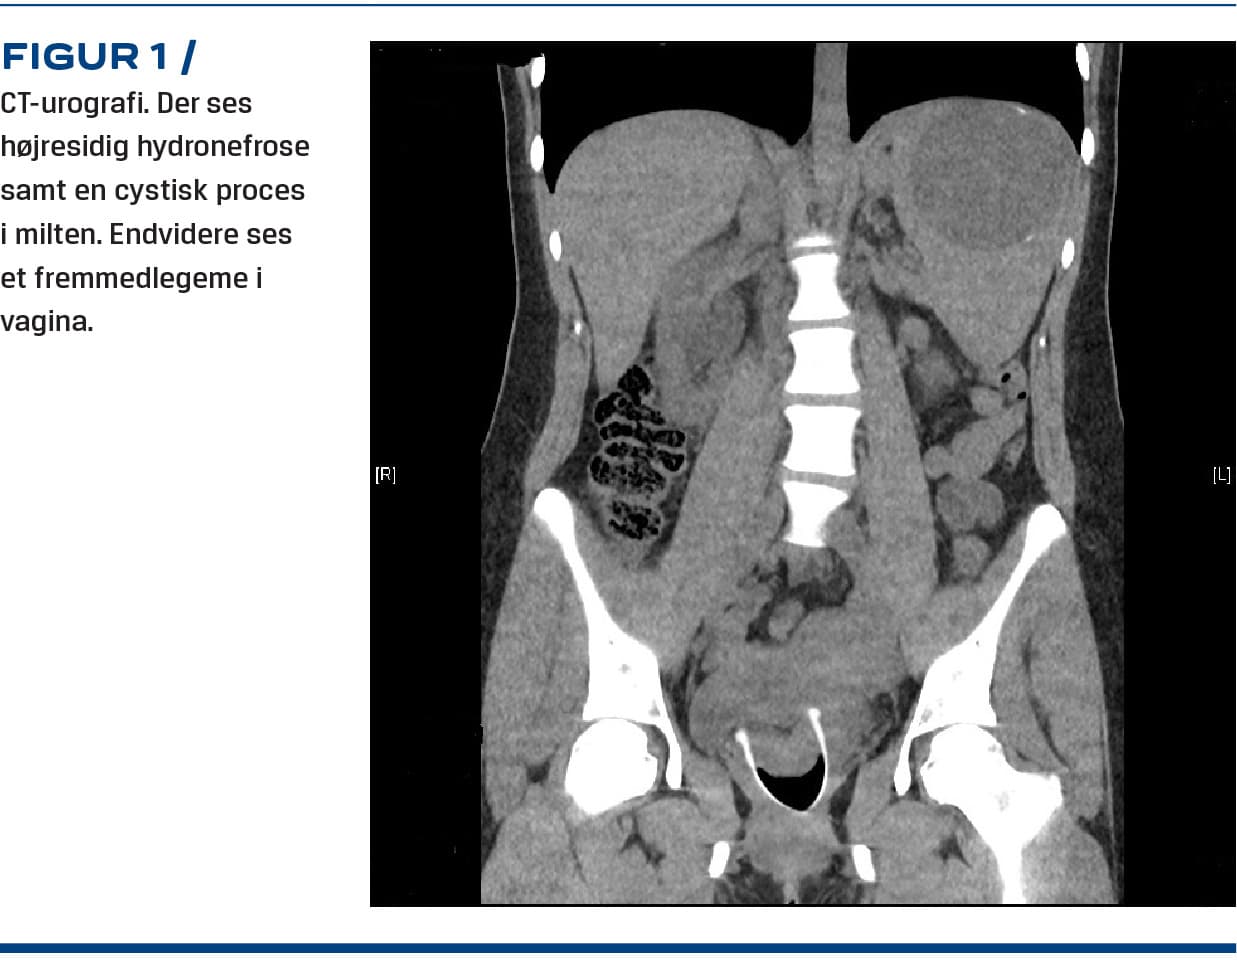

En måned senere henvendte hun sig igen med akkurat samme symptombillede, igen tydeligt smerteforpint, og atter var en urinstikstest positiv for blod. Udredningen blev suppleret med CT-urografi, og denne viste tegn på højresidig hydronefrose samt en cystisk proces i milten. Endelig viste urografien, at der i vagina sad et fremmedlegeme, der tydeligt pressede på højre urinleder (Figur 1). Fremmedlegemet viste sig at være en menstruationskop. Den blev fjernet omgående, hvorefter smerterne aftog kort tid efter. Patienten forblev indlagt til observation natten over og blev udskrevet i velbefindende i habituel tilstand dagen efter.